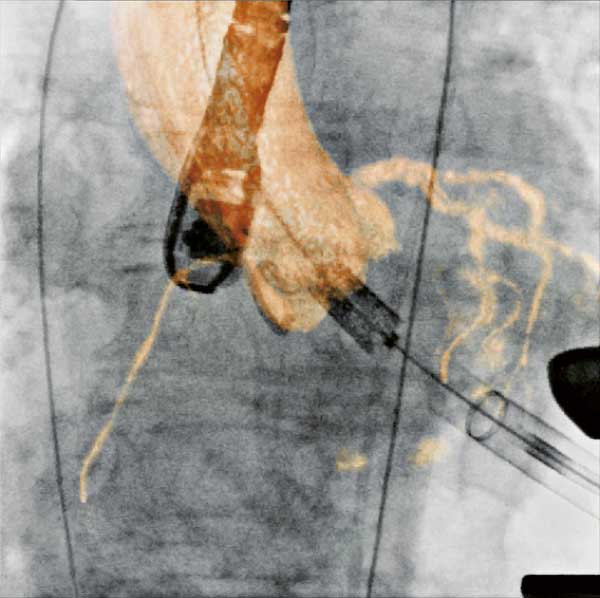

Figure

Figure 2. Aortic stent graft visualized with 3D CT-like imaging. Courtesy of Deutsches Herzzentrum Berlin, Germany Courtesy of Prof. Fosse, Rikshospitalet, Oslo, Norway.

Endovascular aortic repair

Endovascular repair (EVAR) for the abdominal aorta in chronic aneurysms has become a valid alternative to open repair with superior survival (17). EVAR is also increasingly used for the thoracic aorta (Figure 2). In selected cases EVAR in combination with open surgery is even applied for pathologies of the aortic arch and distal ascending aorta (23).